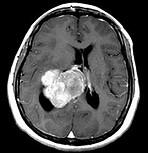

问题 女,45岁,右眼视力下降8个月,右颜面麻木半个月,时有头昏,味觉减退,请根据所提供图像,选择最可能的诊断()

选项 A.(右侧脑室)脑膜瘤(合体细胞型) B.(右侧脑室)室管膜瘤 C.(右侧脑室)脉络膜乳头状瘤 D.(右侧脑室)胶质瘤 E.(右侧脑室)转移瘤

答案 A